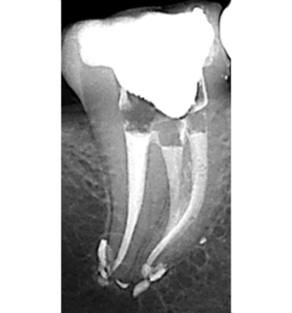

Imagerie en odontologie S3

Endodontie de l'adulte

Imagerie en odontologie S5

Endodontie complexe